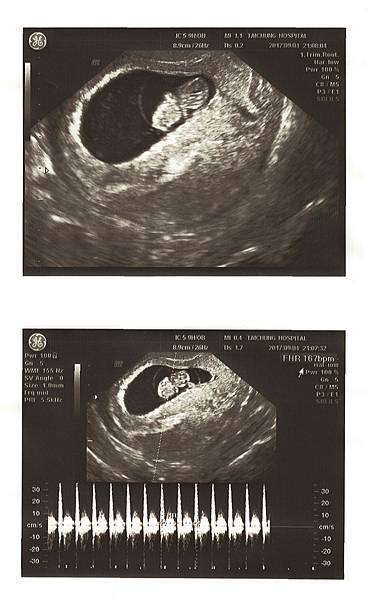

8W3D 9/4回診照心跳,兩週的等待很漫長,到了要照心跳的那天,我和Chris不由自主緊張了起來,也許是上次的經驗讓我們格外緊張與焦慮。一進診間,劉醫師說今天要照心跳喔!

照超音波的時候,醫師一直在肚子上來回滑著儀器,我看著畫面,胚囊明顯變大,但是裡面的東西卻看不清楚,我和Chris開始緊張了起來,躺在診台上的我心臟跳得超快,真的好緊張。

醫師突然請我去廁所把小便解掉,要照陰超看看,還說:照理來說八周應該要有心跳了。聽到這句話的我和Chris整個快無力了~Chris說他當時內心吶喊:不會吧!!

上完廁所後又躺上診台準備照陰道超音波,結果照得好清楚,變大的胚囊裡面已經有胚胎了,劉醫師看著畫面跟我們細心解釋,圓圓的卵黃,是寶寶自己帶的便當,很好喔!

目前大小也在標準值,一邊聽我還是一邊緊張,因為最重要的是我們期待著的心跳聲。接著劉醫師說:來,我們聽聽心跳聲。

“碰碰碰碰碰碰”!好快好有力的聲音,醫師說一分鐘167下,160-180下都是正常的哦!

聽到寶寶心跳聲的當下覺得自己在發抖,也覺得好神奇,肚子裡有了第二個心跳聲。